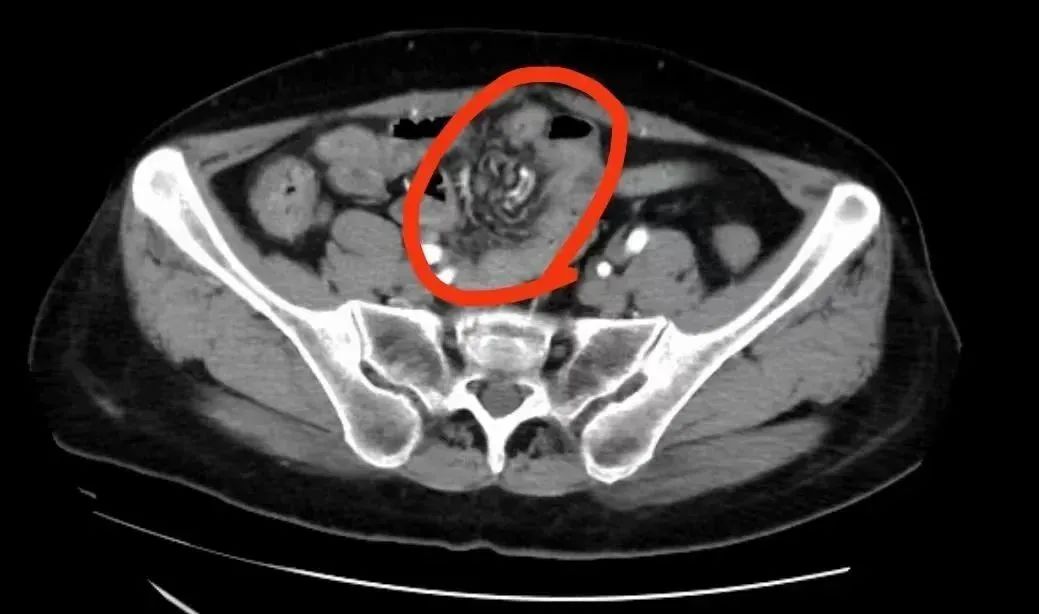

接诊的普通外科医生拿起林姨的 CT 报告,果然发现一系列异常:

首先是她盆腔区域内,有一小段回肠的走行出现了扭曲,这可能是受到某种不明异物的缠绕、牵连。

其次,该区域的肠壁也有增厚的迹象,这表明存在发炎的情况。

综合这些症状,医生判断,这很有可能是腹腔粘连!